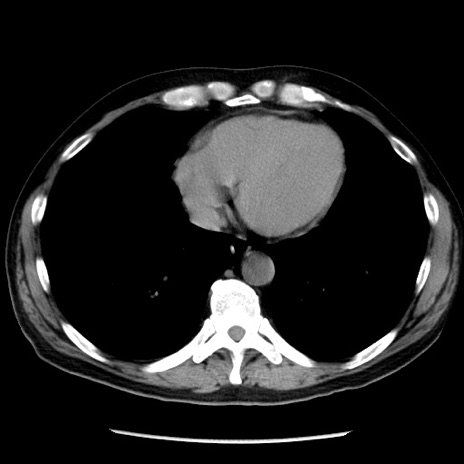

症例29(横断像)

【症例】40歳代男性

【現病歴】2日前から胃痛あり。徐々に周期的な激痛に変化した。本日になっても激痛があるため受診。

【身体所見】意識清明、BT 38-39℃台あり、腹部:膨満、やや硬、右下腹部に圧痛あり。

【データ】WBC 8500、CRP 23.26